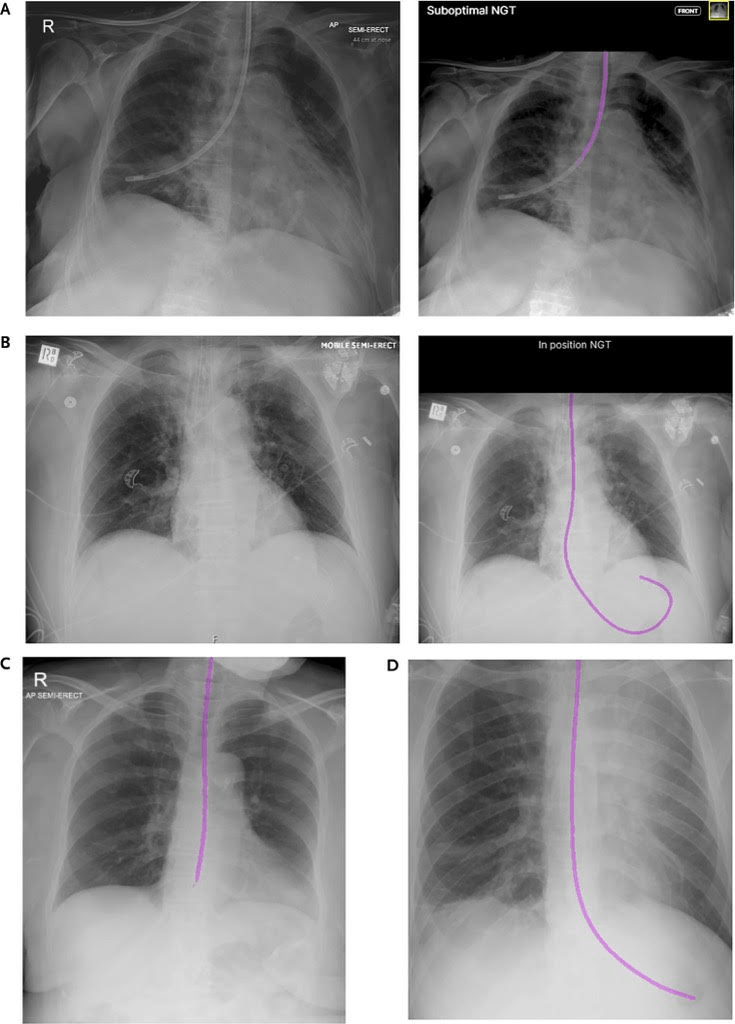

From a February 2026 peer-reviewed research paper on an AI tool for Nasogastric Tube Position, the above image and this disturbing conclusion:

Administration of food or medication through a misplaced nasogastric tube (NGT) constitutes a “never event” (defined by the National Health Service as a serious incident that is wholly preventable) in health care systems given the high likelihood of patient harm. Efforts to ensure adequate NGT positioning typically focus on increased education. Artificial intelligence (AI)–driven decision-support tools could address such challenges in a more streamlined manner, yet external validation studies in real-world settings remain scarce. Our objective was to evaluate the likely impact on patient safety from using an AI tool to detect NGT positioning on chest radiographs (CXRs).

‘The high occurrence of false-negative cases, which could potentially lead to preventable never events, suggests that this AI tool may be unsuitable as a primary decision-support system for NGT placement verification.’